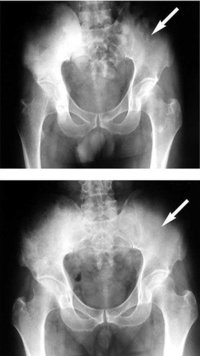

通常の放射線治療はエックス線もしくは電子線という放射線を体の外から照射することが多いのですが、近年になって放射線を出す物質であるラジウムを用いた治療方法が出てきました。このラジウムには骨に集まりやすいという性質があり、体内に投与されるとがんの骨転移している部位など、骨代謝が亢進(こうしん)しているところにこのラジウムが集まります。骨転移巣に集まったラジウムからエックス線の一つであるアルファ線が放出され、骨に転移したがん細胞の増殖を抑え、がんを制御します。アルファ線は、エネルギーが高く、細胞を破壊する力が強いという特徴があります。しかし、アルファ線の力が届く距離は体内では0・1ミリ未満と短いことから、正常細胞に影響を及ぼすことは比較的少ないとされています。

このような点を利用して、ラジウムを注射によって体内に投与すると、体の内側(骨の中)からアルファ線という放射線を出して、骨転移した前立腺がんに対して治療効果を認めます。しかしこの治療は、ホルモン治療などが効かなくなってきた、前立腺がんによる骨転移を有する患者さんにしか保険適応はありません。現在、世界中でこのような治療方法の臨床試験が行われています。今後、このような体内に放射性物質を注射して体の内部からがん治療ができる物質が開発されていくと考えます。